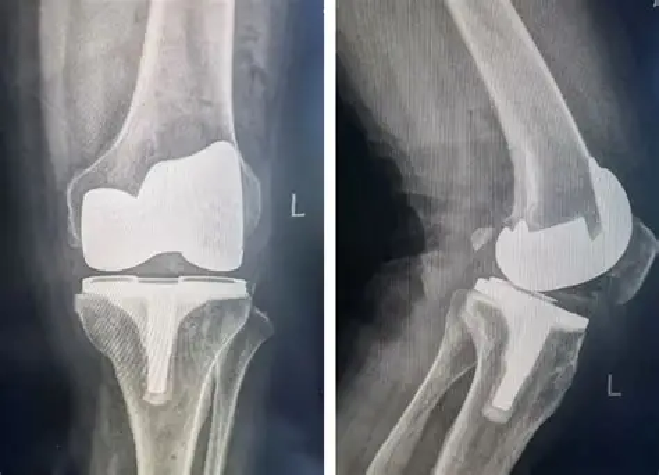

如果已经出现不适,及时干预能有效阻止病情加重。在发病早期,可以遵医嘱服用氨基葡萄糖,这种物质能为软骨提供营养,帮助修复受损组织;同时搭配外用消炎止痛药膏,能快速缓解疼痛。到了中期,关节腔注射玻璃酸钠是个不错的选择,它就像给干涩的关节 “上润滑油”,能增加关节液的黏稠度,减少摩擦。而如果发展到晚期,膝盖疼得连走路都困难,人工膝关节置换术就能解决问题 —— 手术会将磨损的关节面替换成人工假体,术后经过康复训练,患者不仅能正常走路,上下楼梯、散步都不成问题。